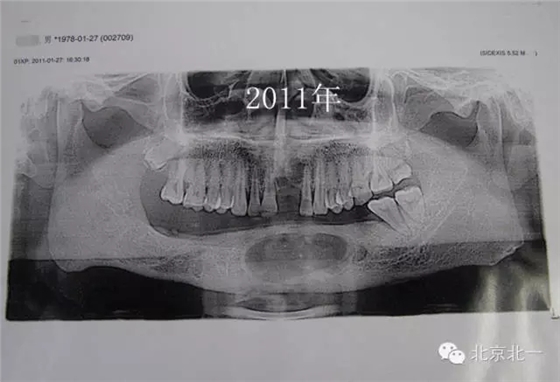

患者男,33歲,左下頜囊腫復發(fā)兩次就診。

圖2、手術后第一次復發(fā)

圖三、再次手術后第二次復發(fā)